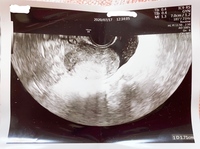

5週0日でこの大きさは小さいですか?流産してしまう確率は高いのでしょうか。5週0日だと平均6ミリ以上とどこかで見たこともあり、ネットで検索しても6ミリ以上の方が多く、とても心配です。 (40代/女性) マスコット先生 産婦人科

このエコー写真に写っているものは胎児ですか 妊娠5週0日目のエ Yahoo 知恵袋

これは胎嚢ですか 妊娠5週0日です これは胎嚢ですか 妊娠5週0日 妊娠 教えて Goo

妊娠5週0日 5w0d の超音波 エコー 写真